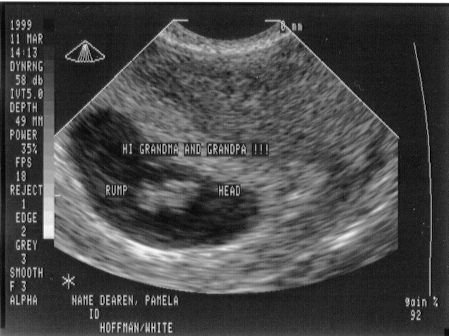

This is me at 7 weeks and 2 days. Mom and Dad got to see my heart beating for the first time.